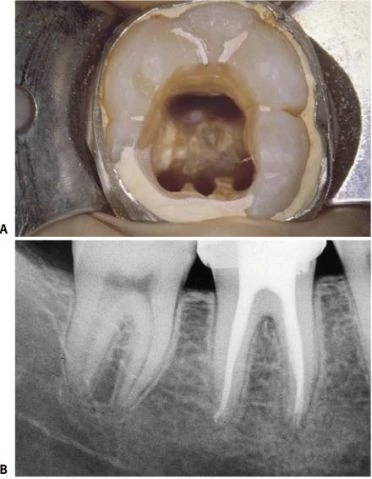

* Những trường hợp khác, chân gần có thể có một ống tủy ở chính giữa, vì vậy răng có một ống tủy ở phía xa và một ống tủy ở phía gần (hình 11.123). Để chắc chắn rằng chân gần có một ống tủy đơn, cần phải kiểm tra vị trí miệng ống tủy ở sàn buồng tủy và chụp X-quang theo nhiều hướng khác nhau. Đôi lúc có thể tìm thấy dấu hiệu thủng sàn ở phía trong xoang tủy do nha sĩ trước đã cố gắng tìm ống tủy gần trong trong khi chân gần chỉ có một ống tủy.

Hình 11.123. Răng cối lớn thứ hai hàm dưới với một ống tủy ở chân xa và một ống tủy ở chân gần. A. Xoang tủy: Hai ống tủy tại đáy của rãnh nằm giữa sàn tủy. Bên phải có dấu của mũi khoan (hướng về mặt lưỡi). Nha sĩ trước đó đã cố tìm ống tủy gần trong vốn không tồn tại. B. Phim sau điều trị: hai ống tủy nằm ở hai chân răng riêng biệt, thông nhau rõ ràng ở vị trí lỗ chóp của hai chân.